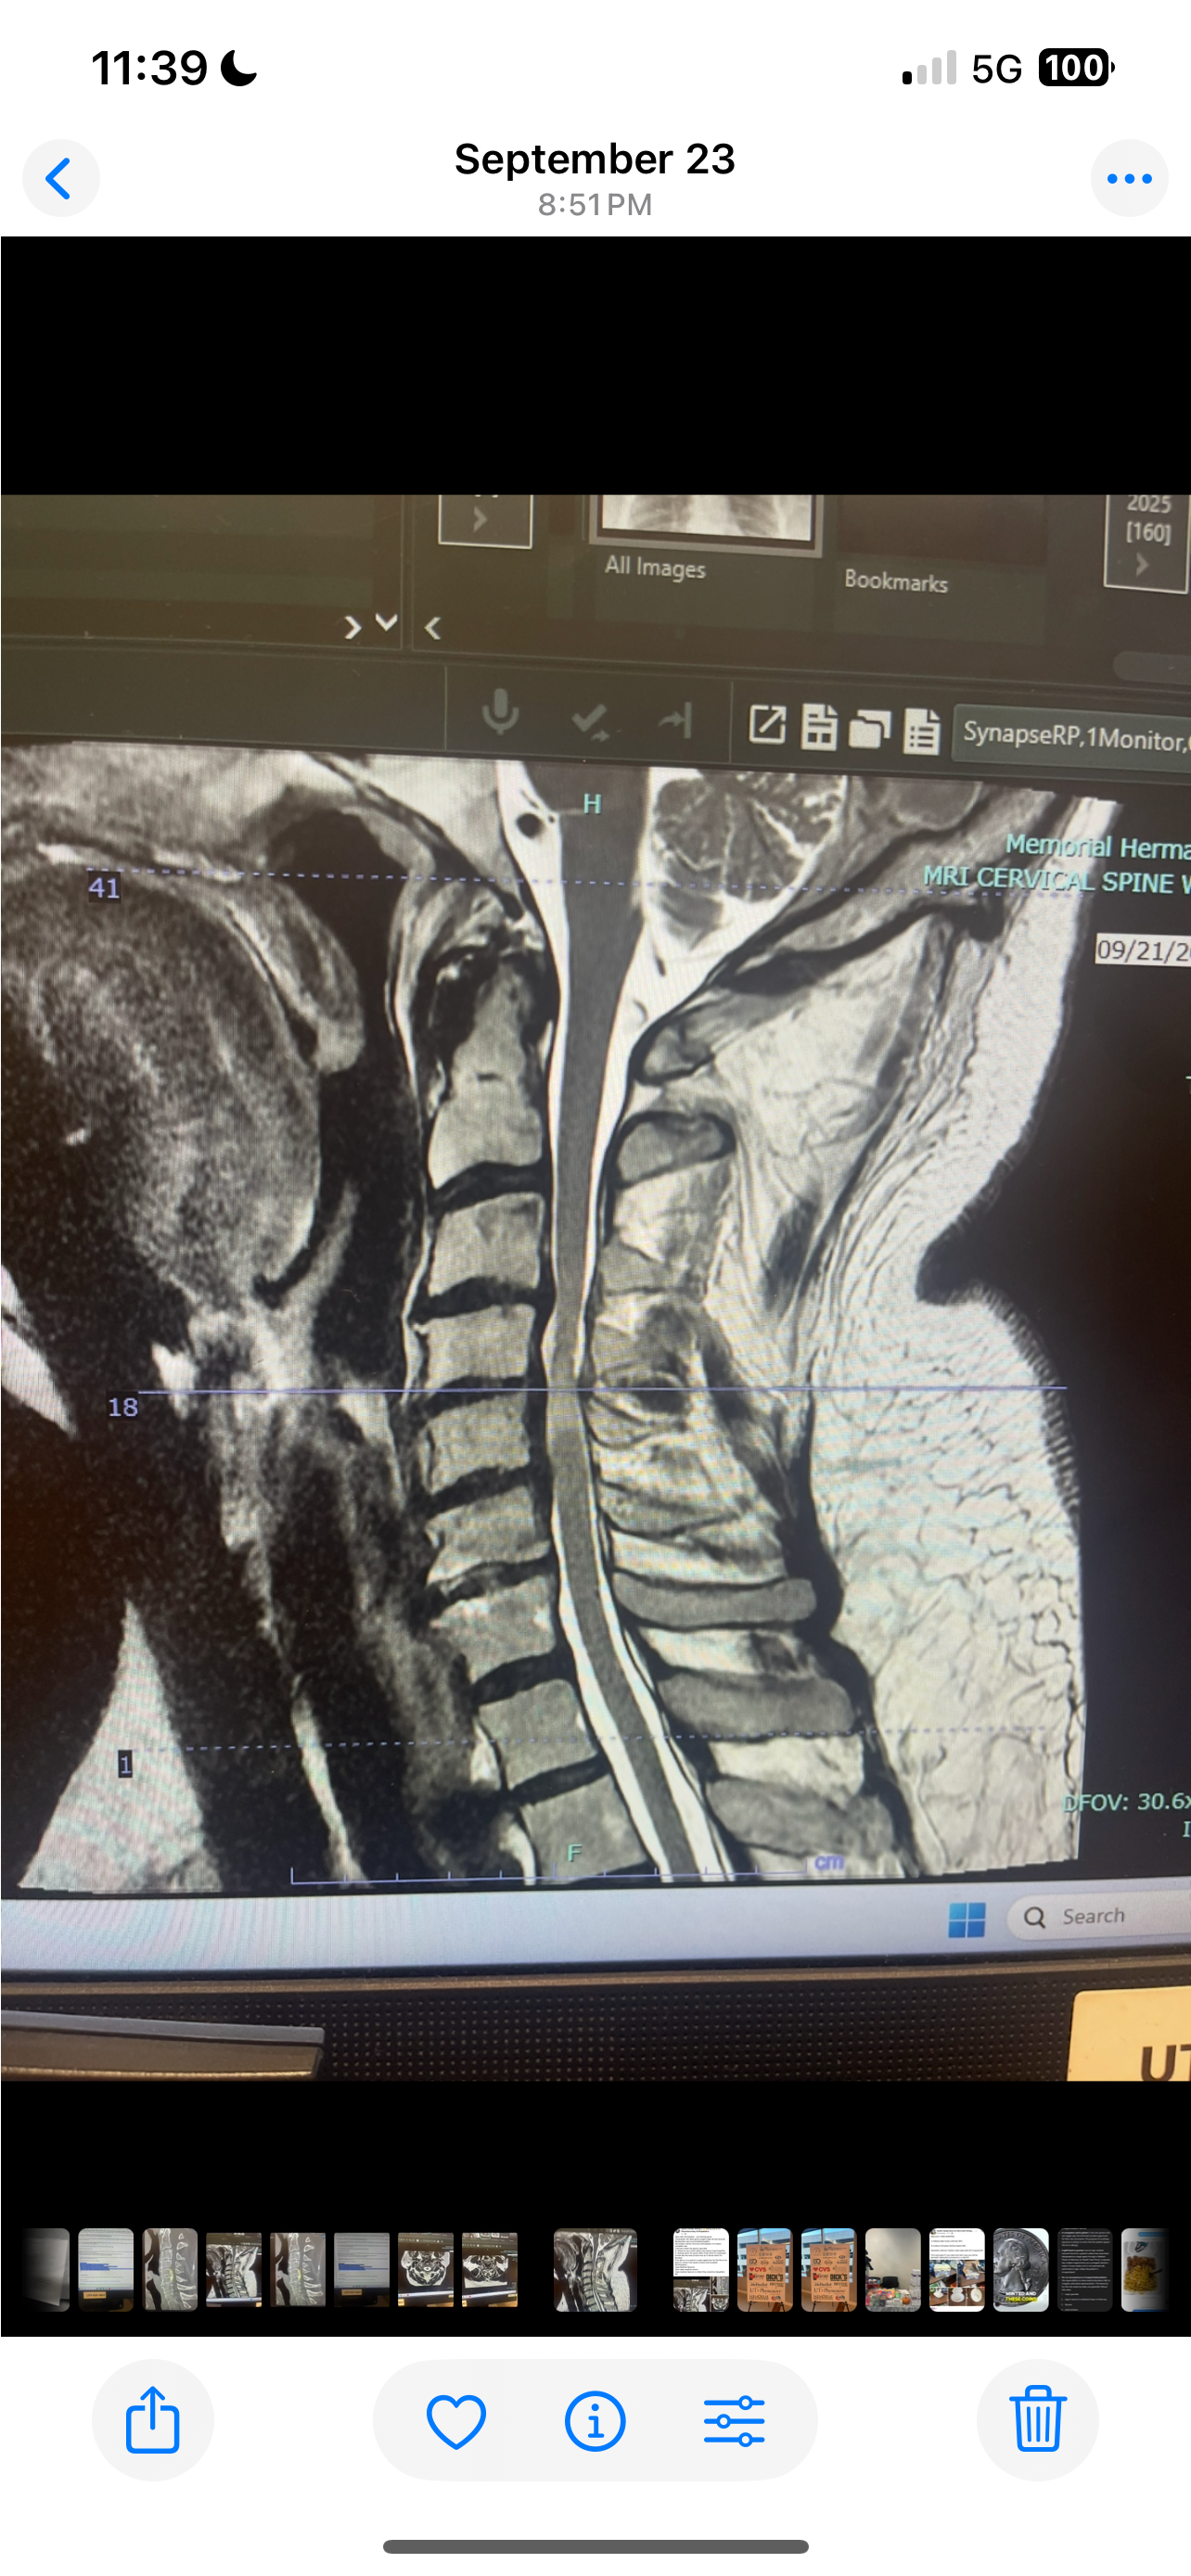

Hello, my name is Karen, and I am raising money for my boyfriend, Christopher Stanley. After months of doctor visits, countless tests, and several MRIs, we finally received answers about what’s been causing Chris so much pain. Earlier this year, he woke up one morning unable to lift his left arm. We rushed to the hospital, but no one could determine what was wrong. Since last February, he’s been living with constant pain and frustration as we searched for answers. We finally found an incredible doctor at Memorial Hermann who discovered that Chris has damage to his spinal cord and two areas in his neck that never fused properly — something he was born with. Both of these issues now need to be repaired through surgery scheduled for December . The recovery process will take about six months, during which he’ll be unable to work. Chris is a devoted life skills teacher who loves his students deeply. He’s the kind of teacher who always goes above and beyond to help others, and now he’s the one who needs a little help. We’re raising funds to help cover his surgery deductible, as well as the expenses before and after surgery — including bills while he’s unable to work, medical needs, and a new adjustable bed to help with his recovery. We’re also working on organizing a community fundraiser with a barbecue, silent auction, and live music to support him through this time. This surgery is critical. The doctor explained that without it, even a small fall or bump could leave him permanently paralyzed. As scary as that is, we’re beyond grateful that we finally have answers and a skilled surgeon who can help him heal and hopefully regain full use of his arm. If you’re able to donate or simply share this GoFundMe, we would be so deeply thankful. Every bit of support — financial or emotional — means the world to us. Thank you from the bottom of our hearts for helping Chris get the care he needs and for standing by us on this journey.